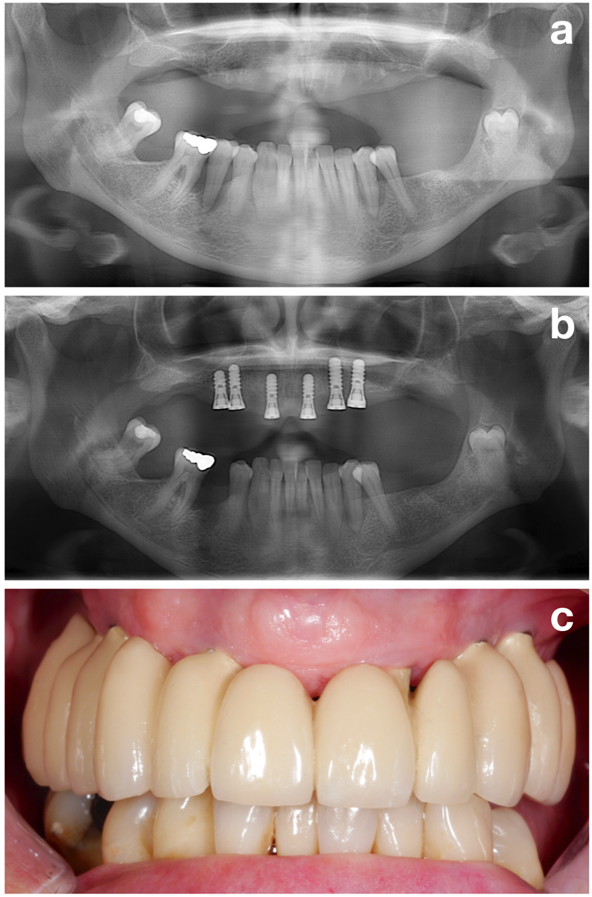

La méthode NIWOP (Figure 1) s’articule autour de 3 axes principaux : (1) Phase de prétraitement, (2) pose de l’implant et (3) suivi ou traitement de soutien.

La première phase (c’est-à-dire le prétraitement) a pour but de préparer le patient de façon optimale en vue de l’implantation en évaluant tous les facteurs de risque potentiels mais en ciblant l’un des objectifs plus importants, à savoir l’établissement d’une situation parodontale stable (Figure 2).

En conclusion, conjugué à d'autres objectifs, tels que l'arrêt du tabac ou une hygiène buccodentaire irréprochable (Figure 3), l'établissement d’une situation parodontale stable est l’un des objectifs les plus importants de la phase de prétraitement, qui doit être atteint avant l’implantation !